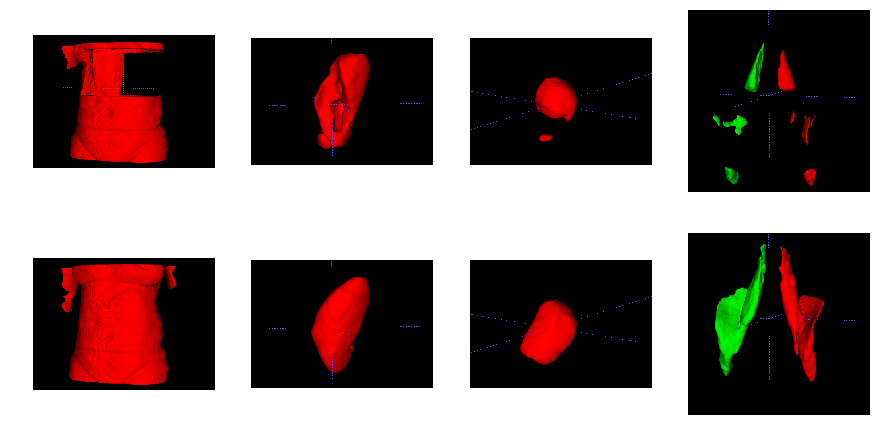

Fig. 3 shows the ground-truth data, predictions and their absolute difference for the fat and water channels of a participant in the testing set. Model predictions and the original data from the scanner for participants affected by various fat-water swaps are provided in Fig. 4. The examples were selected to illustrate the performance of our model in a variety of scenarios: data that are not affected by major swaps, data affected by swaps that cover an entire series in the acquisition (Fig. 4 a, c), as well as data displaying complex partial (Fig. 4 b, d, e) and/or boundary swaps (Fig. 4 f, g). The absolute difference images in columns 3 and 6 of Fig. 4 highlight where the original data have been affected by a fat-water swap in the scanner reconstruction but the model correctly predicted the fat and water channels. Fig. 5 provides examples of 3D segmentations using data that suffered from fat-water swaps (top row) and the segmentation when using our model predictions (bottom row) for the following organs and tissue (from left to right): abdominal subcutaneous adipose tissue, left kidney, spleen, and left/right iliopsoas muscles (red and green, respectively). The predictions shown in Figs. 3 and 4, as well as the underlying volumes used for the 3D segmentations in Fig. 5, are outputs of the final dual-input model, which performed the best across all of our experiments.

Our assessment of false positive rate between the dixonfix method [13] and our method using 50 out-of-sample subjects that were free of swaps, has shown that our model induced zero false positives. On average, the dixonfix method induced 4.29 swaps inside the body, with an average misclassification of voxels per subject, equivalent to an error rate of 0.074% over the entire volume (including background voxels).

We have shown that our single- and dual-input models are able to predict swap-free fat and water volumes. Processing the entire neck-to-knee volumes, for example those found in the UK Biobank abdominal protocol, takes approximately eight seconds per scan. We have established the high quality of our results through quantitative metrics such as PSNR and SSIM (with average values consistently ) for the dual-input model in both cross-validation experiments (Table 1) and out-of-sample test data on final versions of the models (Table 2). We have shown qualitative performance on scans where the scanner software failed to adequately separate the fat and water channels during reconstruction in visual examples (Fig. 3) and by comparing to dixonfix to establish our method does not induce fat-water swaps (false positives). As a final qualitative validation we used the predicted channels as input to 3D segmentation models and have shown how the corrected data produces superior segmentations.

When assessing the false positive rate of our model and comparing it to the dixonfix method, no false positives were detected while the latter introduced on average an error of approximately incorrectly-swapped voxels per subject, corresponding to roughly in volume. This could have a significant impact on downstream analyses of structures such as visceral adipose tissue, muscles and in particular smaller abdominal organs (liver, spleen, kidneys, etc). While the authors in [13] pointed out that all swaps were corrected, they did underline the fact that every prediction induced false positives in the 3D volume. These incorrectly-swapped voxels may appear in unimportant areas of the data, but we observed some induced swaps in structures such as skeletal muscle and adipose tissue. Depending on the downstream analyses performed after fat-water swap correction, such small errors may be acceptable. Further assessment on the impact of fat-water swap corrections with consistent false positives or false negatives (i.e., fat-water swaps that are ignored) in large-scale population studies is an interesting direction of investigation but outside the scope of this work.